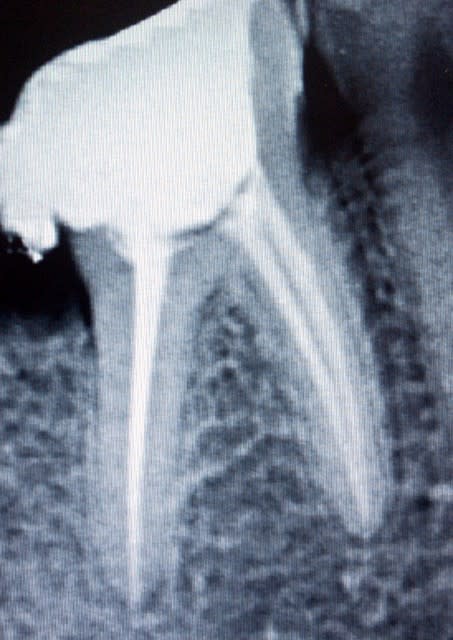

Ci joint une RX post op d'une reprise de traitement que j'avais fait au R endo il y a 1 an 1/2.

Rdiologiquement, c'est correct mais c'est tout.

P.S: au dessus, c'est du cavit... je précise...